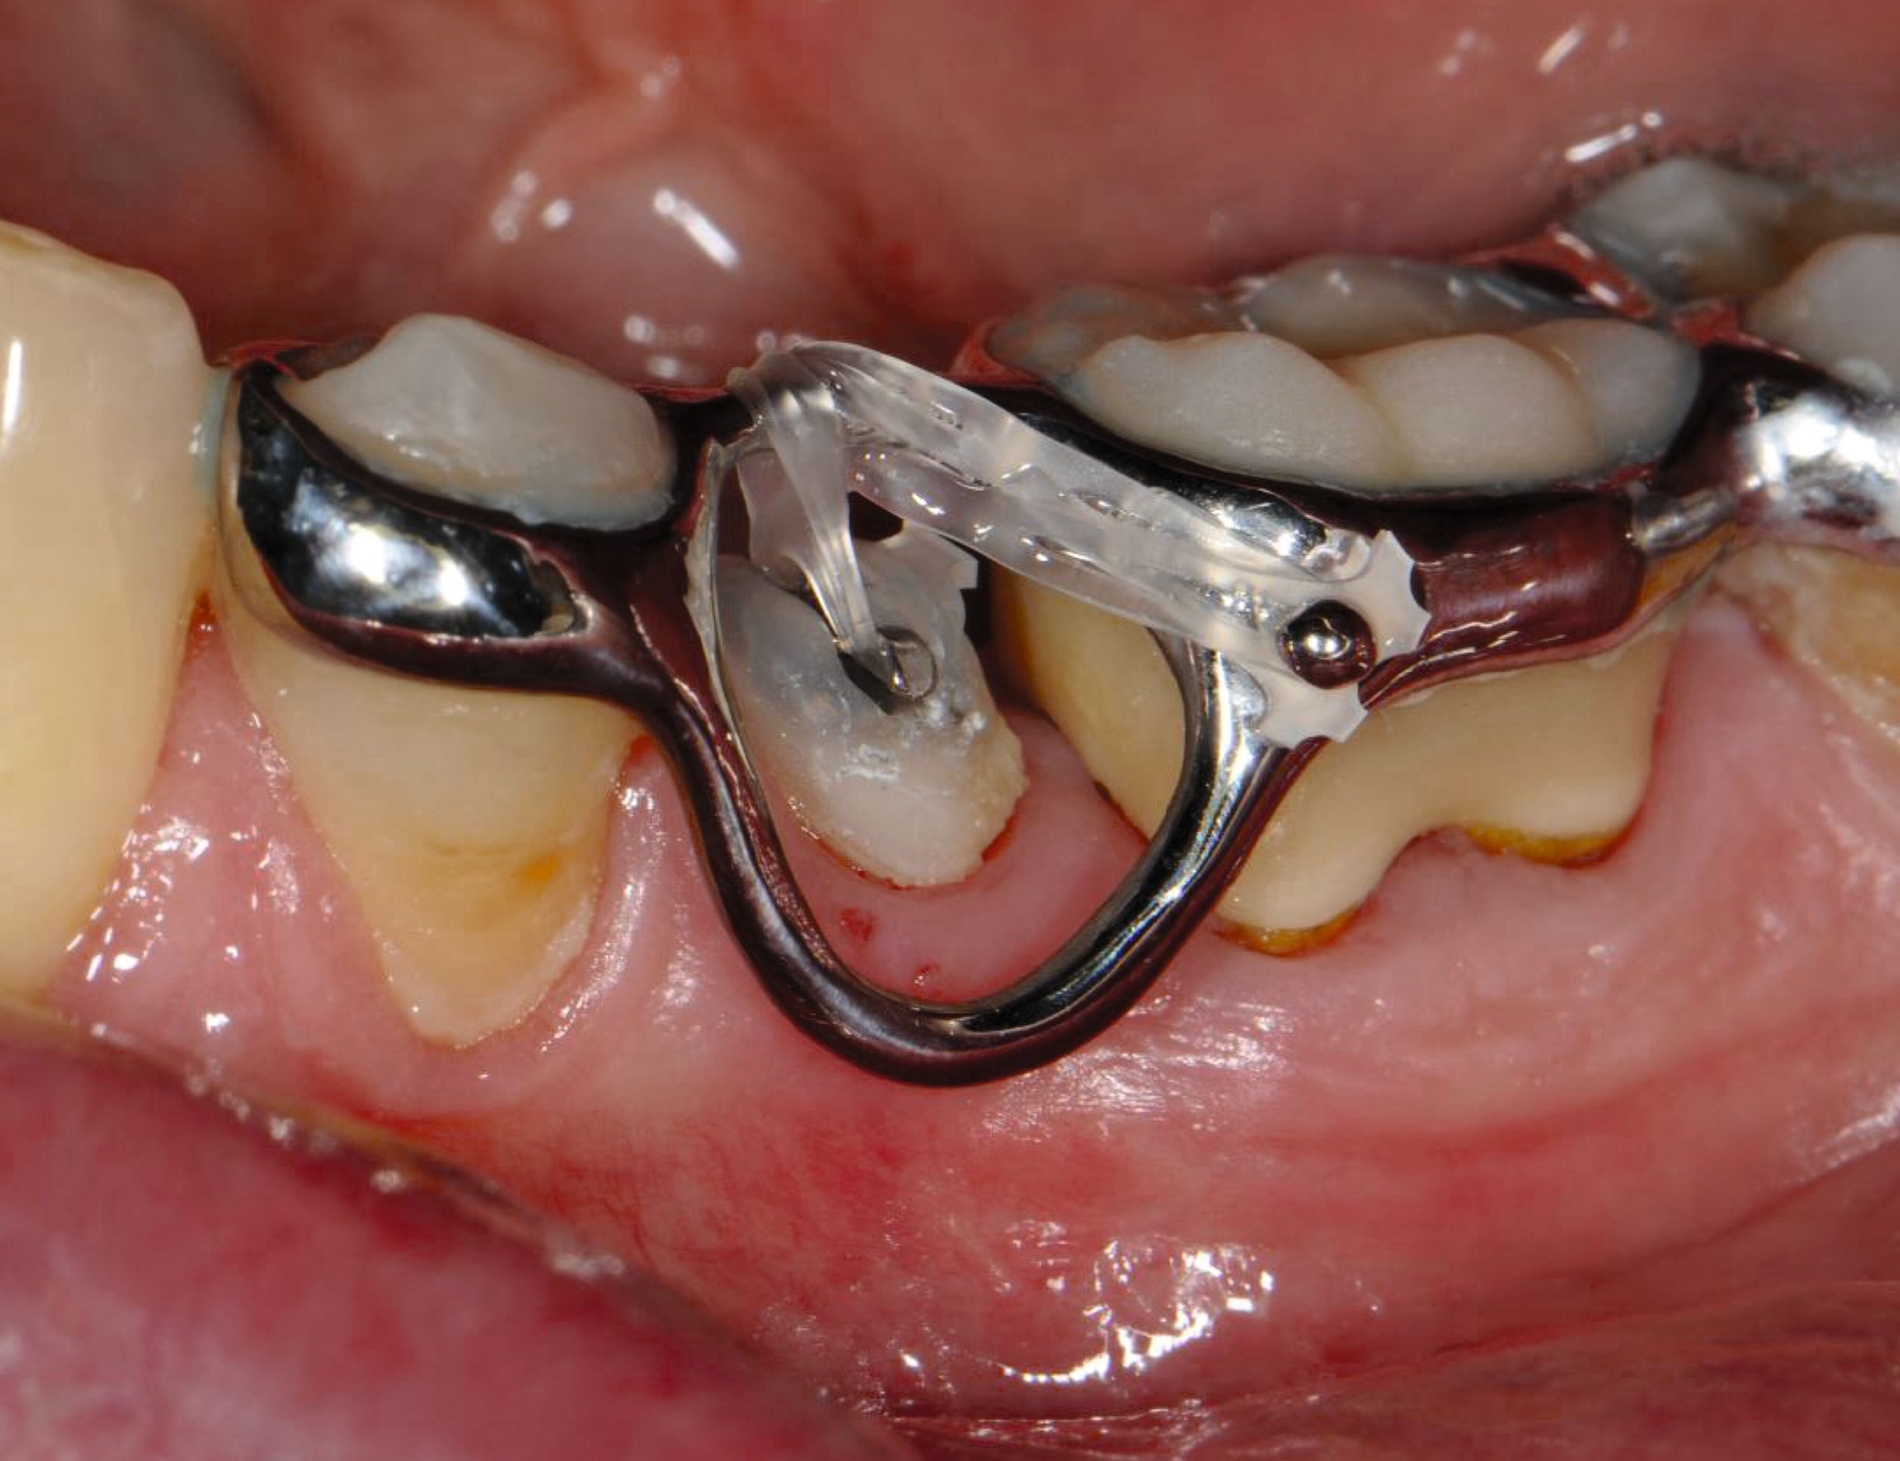

Auch die Herstellung zusätzlicher Elemente, wie beispielsweise Transpalatinalbögen aus Keramik-gefüllten 3-D-Druckkunststoffen, ist möglich (Abbildung 2c) [Thurzo et al., 2022], muss jedoch in großangelegten Studien noch auf eine ausreichende klinische Suffizienz untersucht werden. Weiter bieten 3-D-gedruckte Transferguides die Möglichkeit des „Indirekten Klebens“ [Deahl et al., 2007; Bozelli et al., 2013; Li et al., 2019; Sabbagh et al., 2022], wobei die Bracketpositionierung bereits vor dem Einsatz digital festgelegt und schließlich durch den Transferguide intraoral übertragen wird (Abbildung 2d). Neben einer verkürzten Stuhlzeit erlaubt dieses Verfahren eine besonders hohe Genauigkeit der Bracketpositionierung.